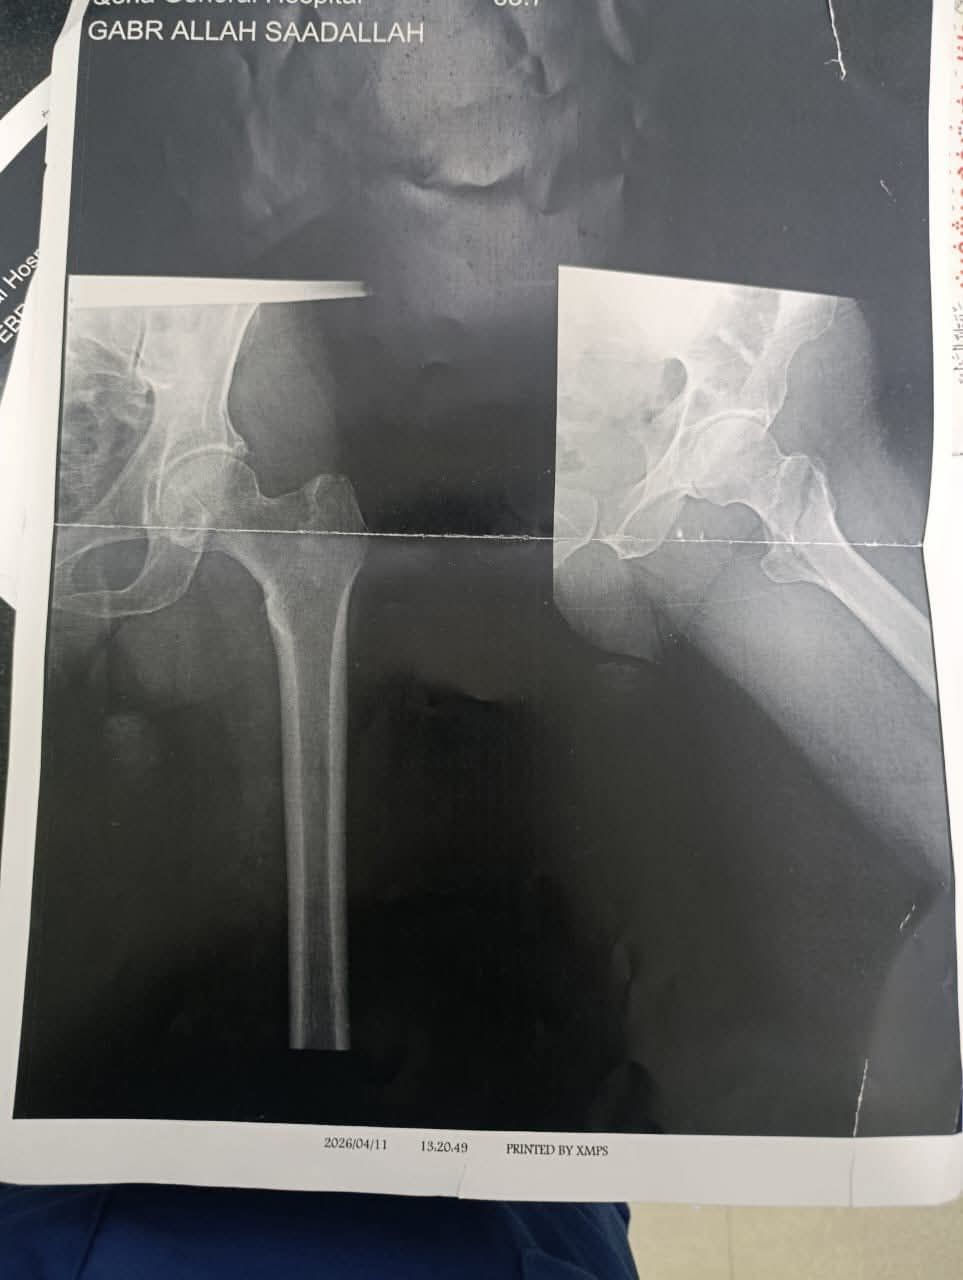

حيث تم إجراء جراحة تغيير نصف مفصل ثنائي القطبين لسيدة تبلغ من العمر 85 عامًا كانت تعاني من كسر بعنق عظمة الفخذ، وخرجت الحالة مستقرة بعد الجراحة.

كما تم إجراء عملية تثبيت كسر بمدور عظمة الفخذ لرجل يبلغ من العمر 75 عامًا باستخدام الشرائح والمسامير، مع تحسن ملحوظ واستقرار الحالة.